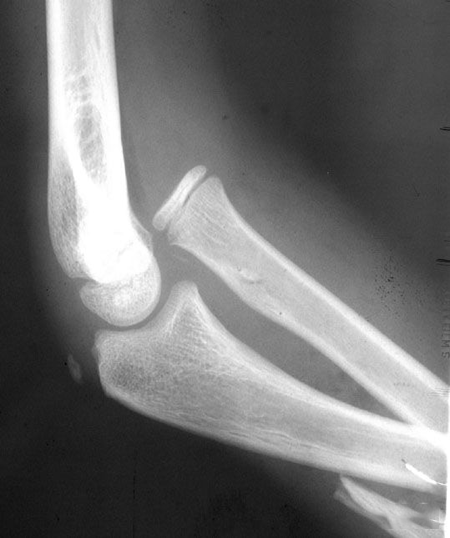

(7)Hahn-steinthal 骨折

全肱骨小头骨折,为一种少见的关节内骨折,多见于成年人。常由于跌倒时手过度伸直或在屈肘时因桡骨小头撞击肱骨小头,并同时有外翻力存在时发病,亦可伴有滑车骨折与内侧副韧带的撕裂。

例 1:肱骨小头基底部呈冠状面骨折,骨折块呈半球状向肘前上方移位。